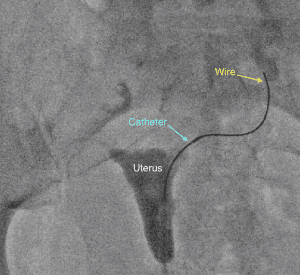

During the procedure, similar to a pelvic exam at your OBGYN, you lay on your back and a speculum is placed into the vagina. Then a small catheter is inserted through the cervix and a contrast agent, or dye, is injected into the uterus so an X-ray image of the uterine cavity can be obtained. When a fallopian tube blockage is identified, another smaller catheter and wire are threaded into the fallopian tube to open the blockage.